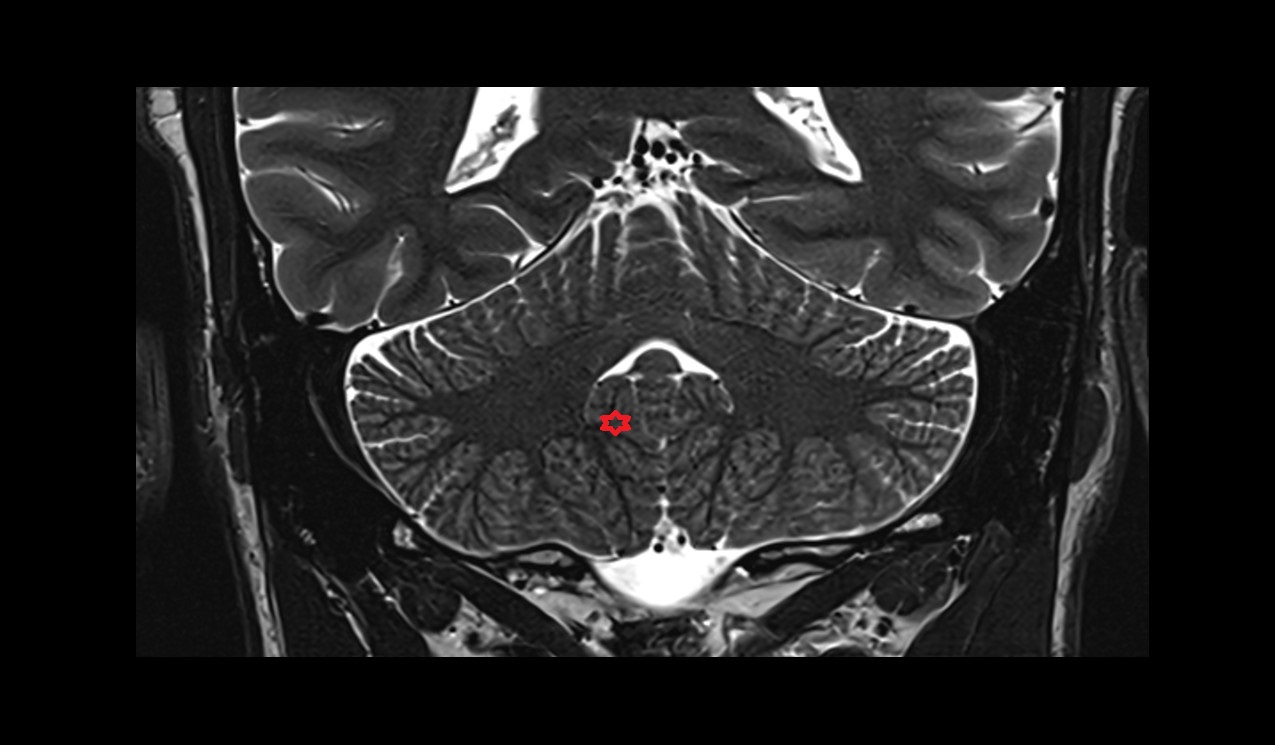

- Cerebellum

- Cerebellar tonsil (H IX)